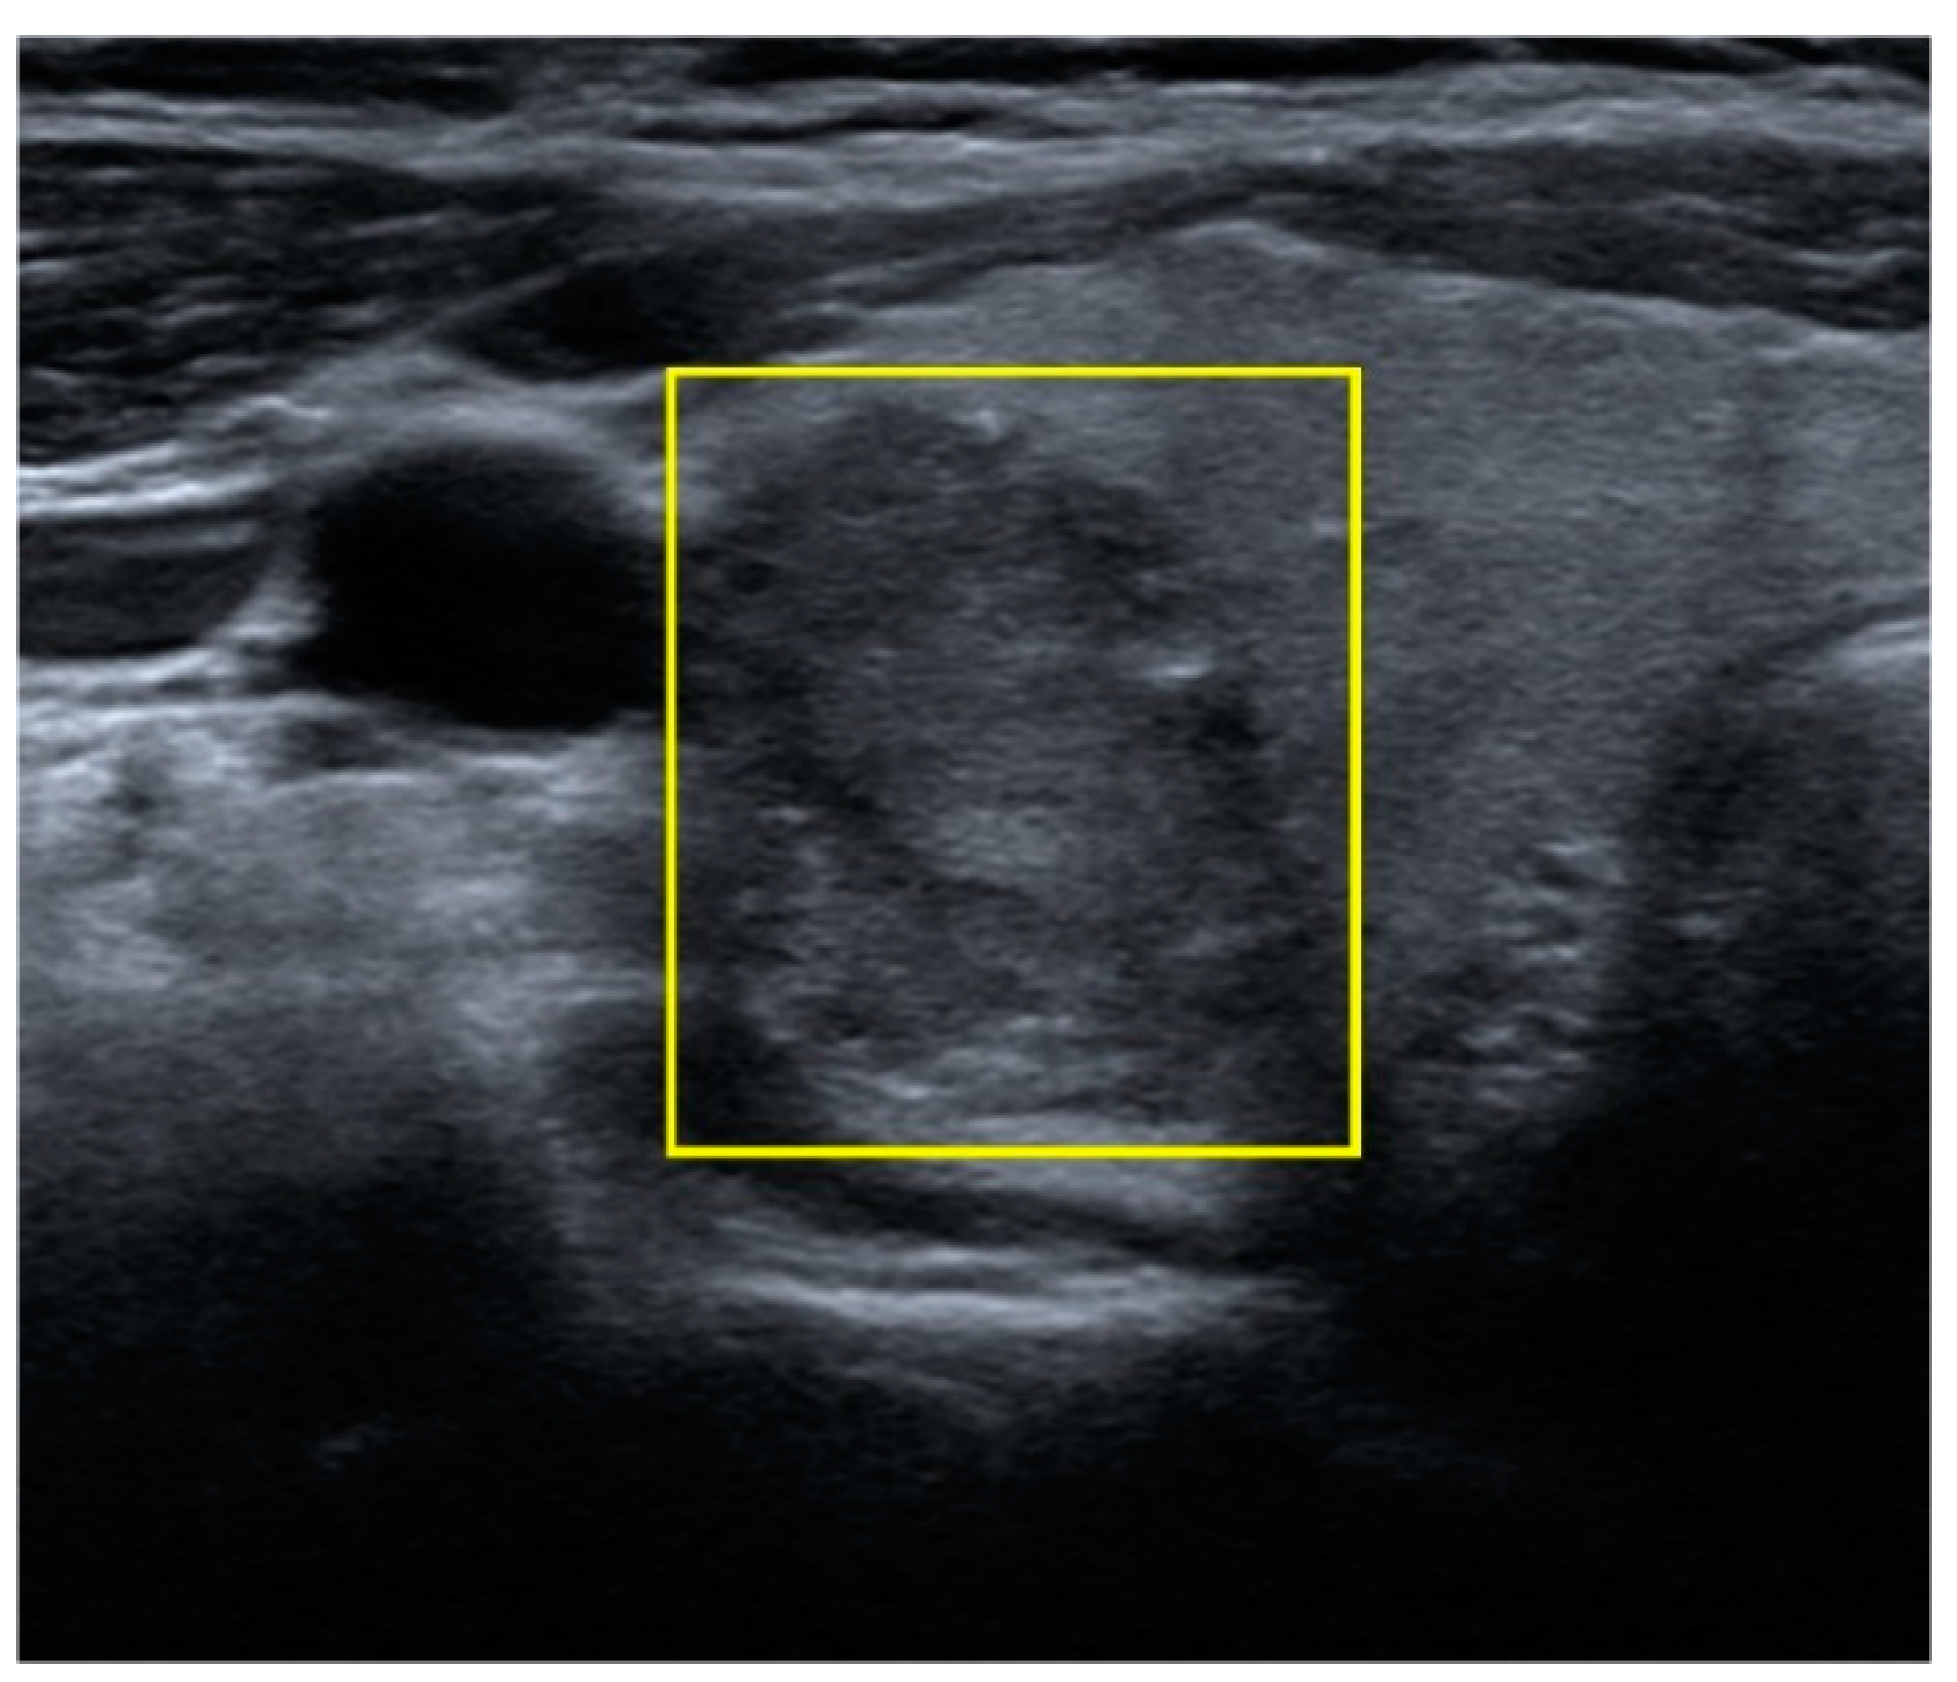

Using Deep Convolutional Neural Networks for Enhanced Ultrasonographic Image Diagnosis of Differentiated Thyroid Cancer

2. Materials and Methods

2.2. Data Collection